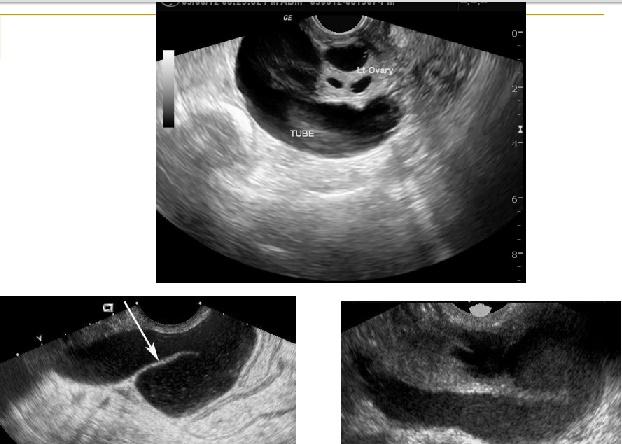

Piosálpinx

Es una acumulación de

material purulento en la trompa de falopio.

Es una secuela de una infección no tratada.

Sonográficamente observamos

las trompas de falopio dilatadas con fluido llenos de ecos internos. Las paredes se observan engrosadas y nodulares.

En estados severos podemos observar un fluido ecogénico, denso y grueso dentro de la trompa y o donde no observamos enhancement posterior